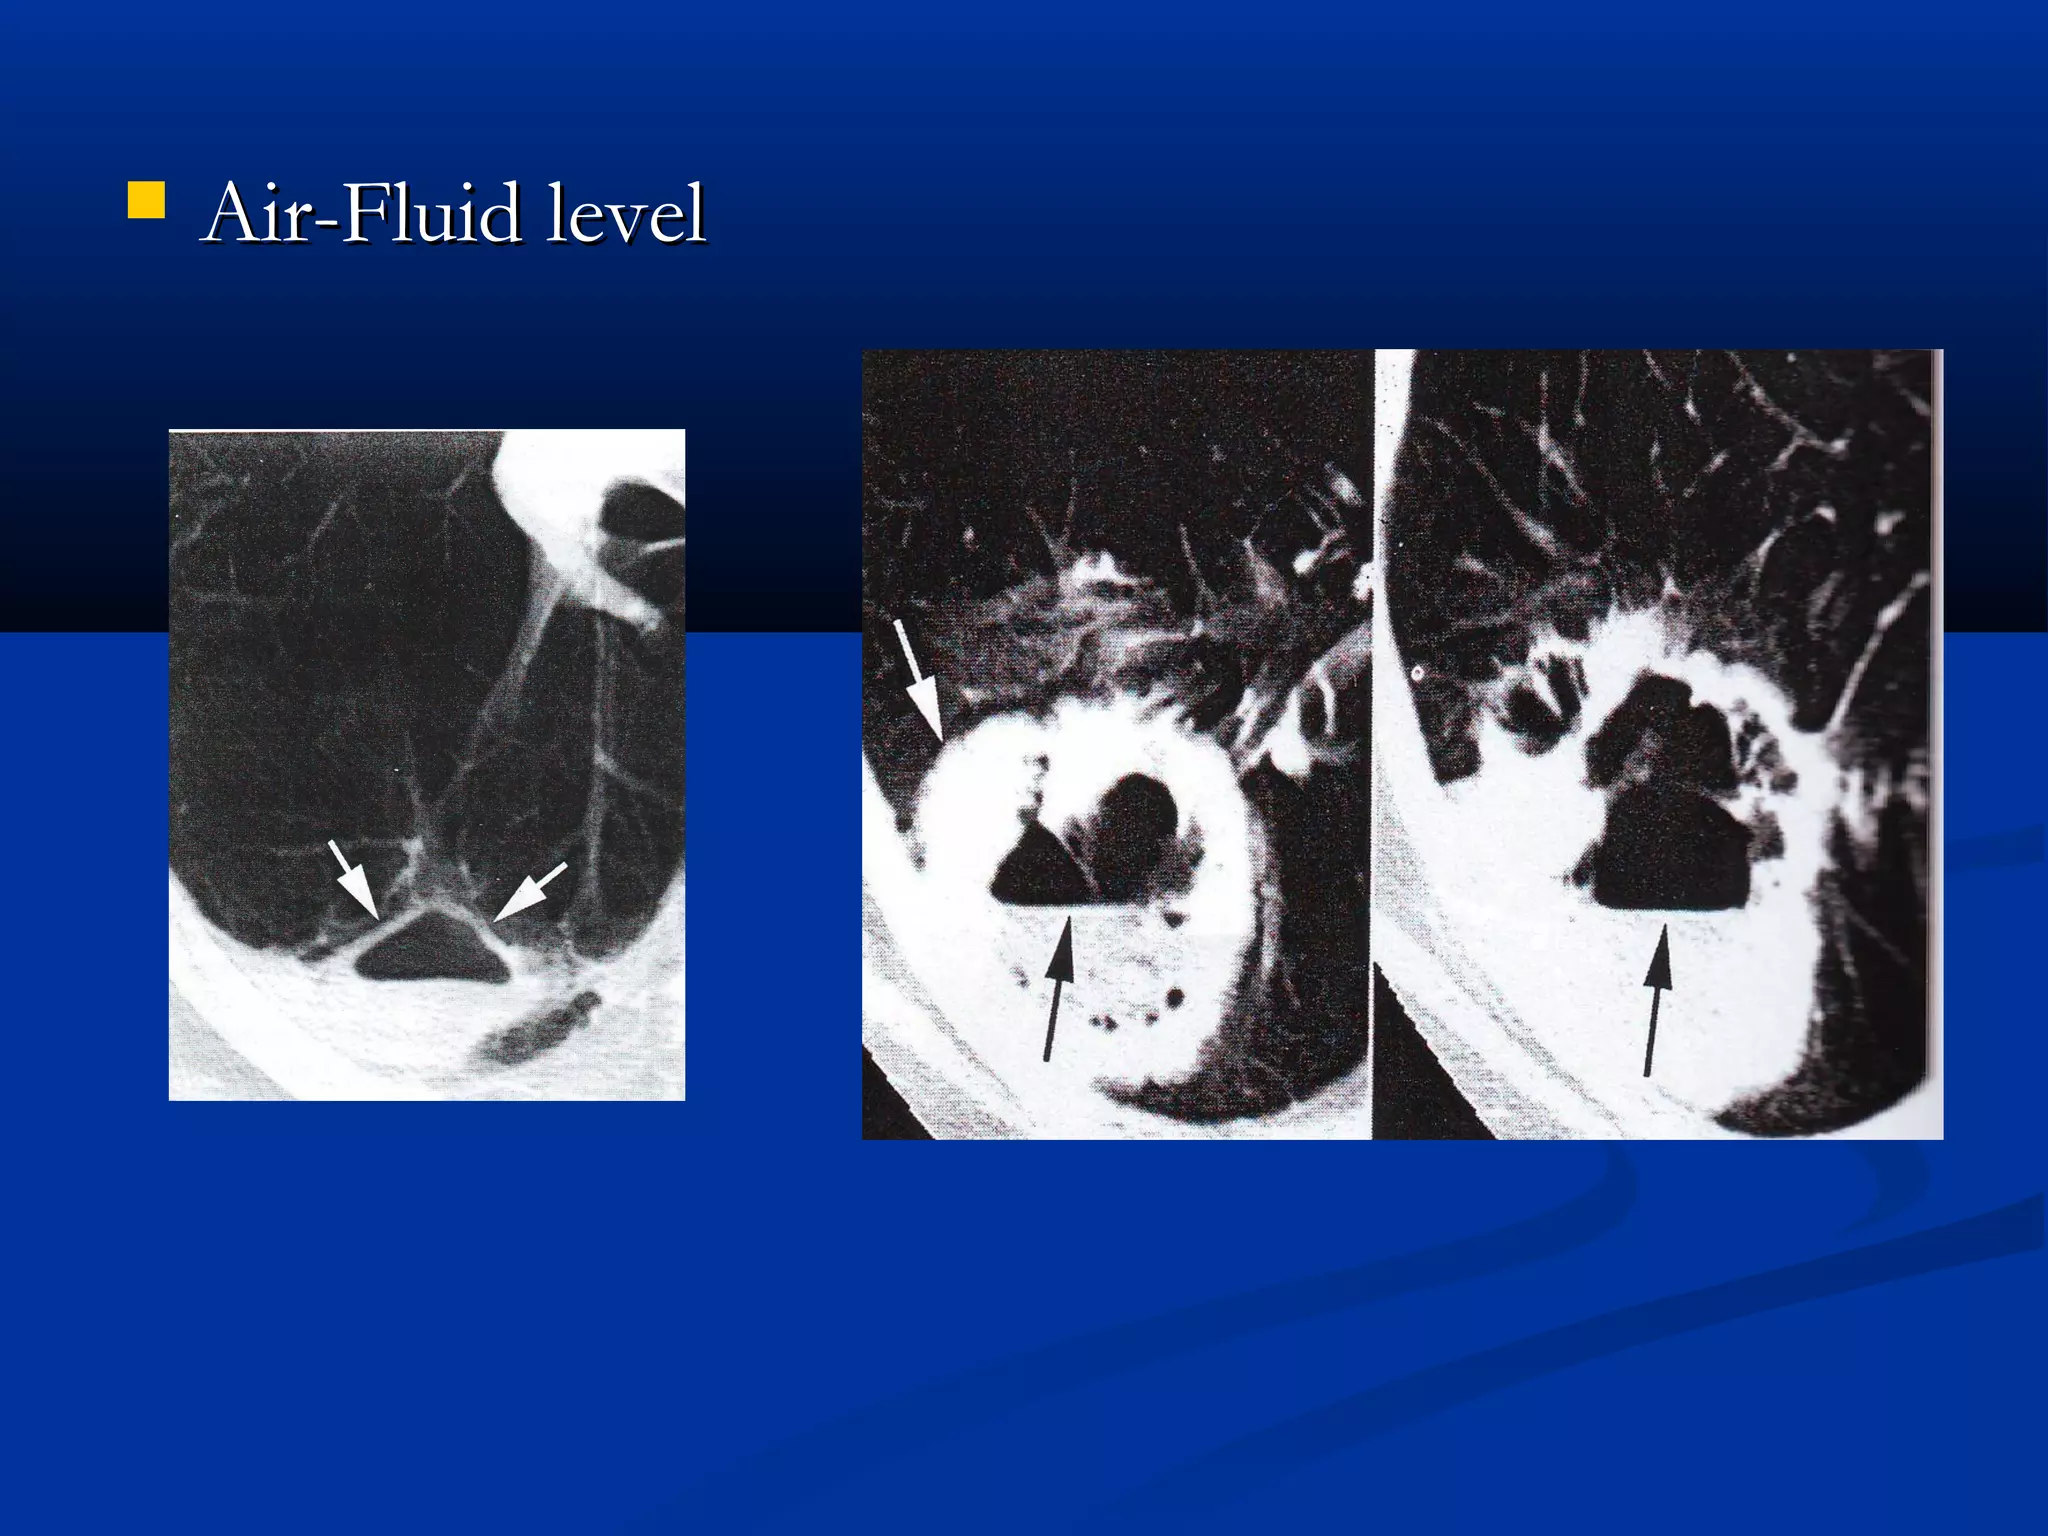

   Air-Fluid level

Air-Fluid level